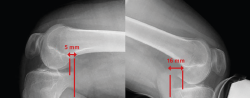

Posterior translation of the tibia is measured as the minimum distance between a line tangential to the posterior cortical layer of the tibia and another line tangential to the posterior margin of the femoral condyle at the most dorsal point of the Blumensaat line (Figure 5)(12,13).

Figure 5. Telos system. The red line indicates measurement of posterior translation of the tibia: the difference between the healthy right knee and the left knee is 11 mm in this case - suggestive of isolated complete posterior cruciate ligament (PCL) rupture.